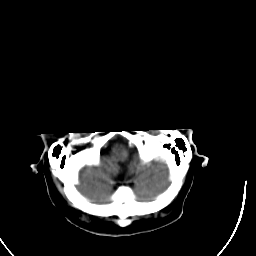

Stroke CT #3 -- Slice #1

[Home][Help][Clinical] Slice 1